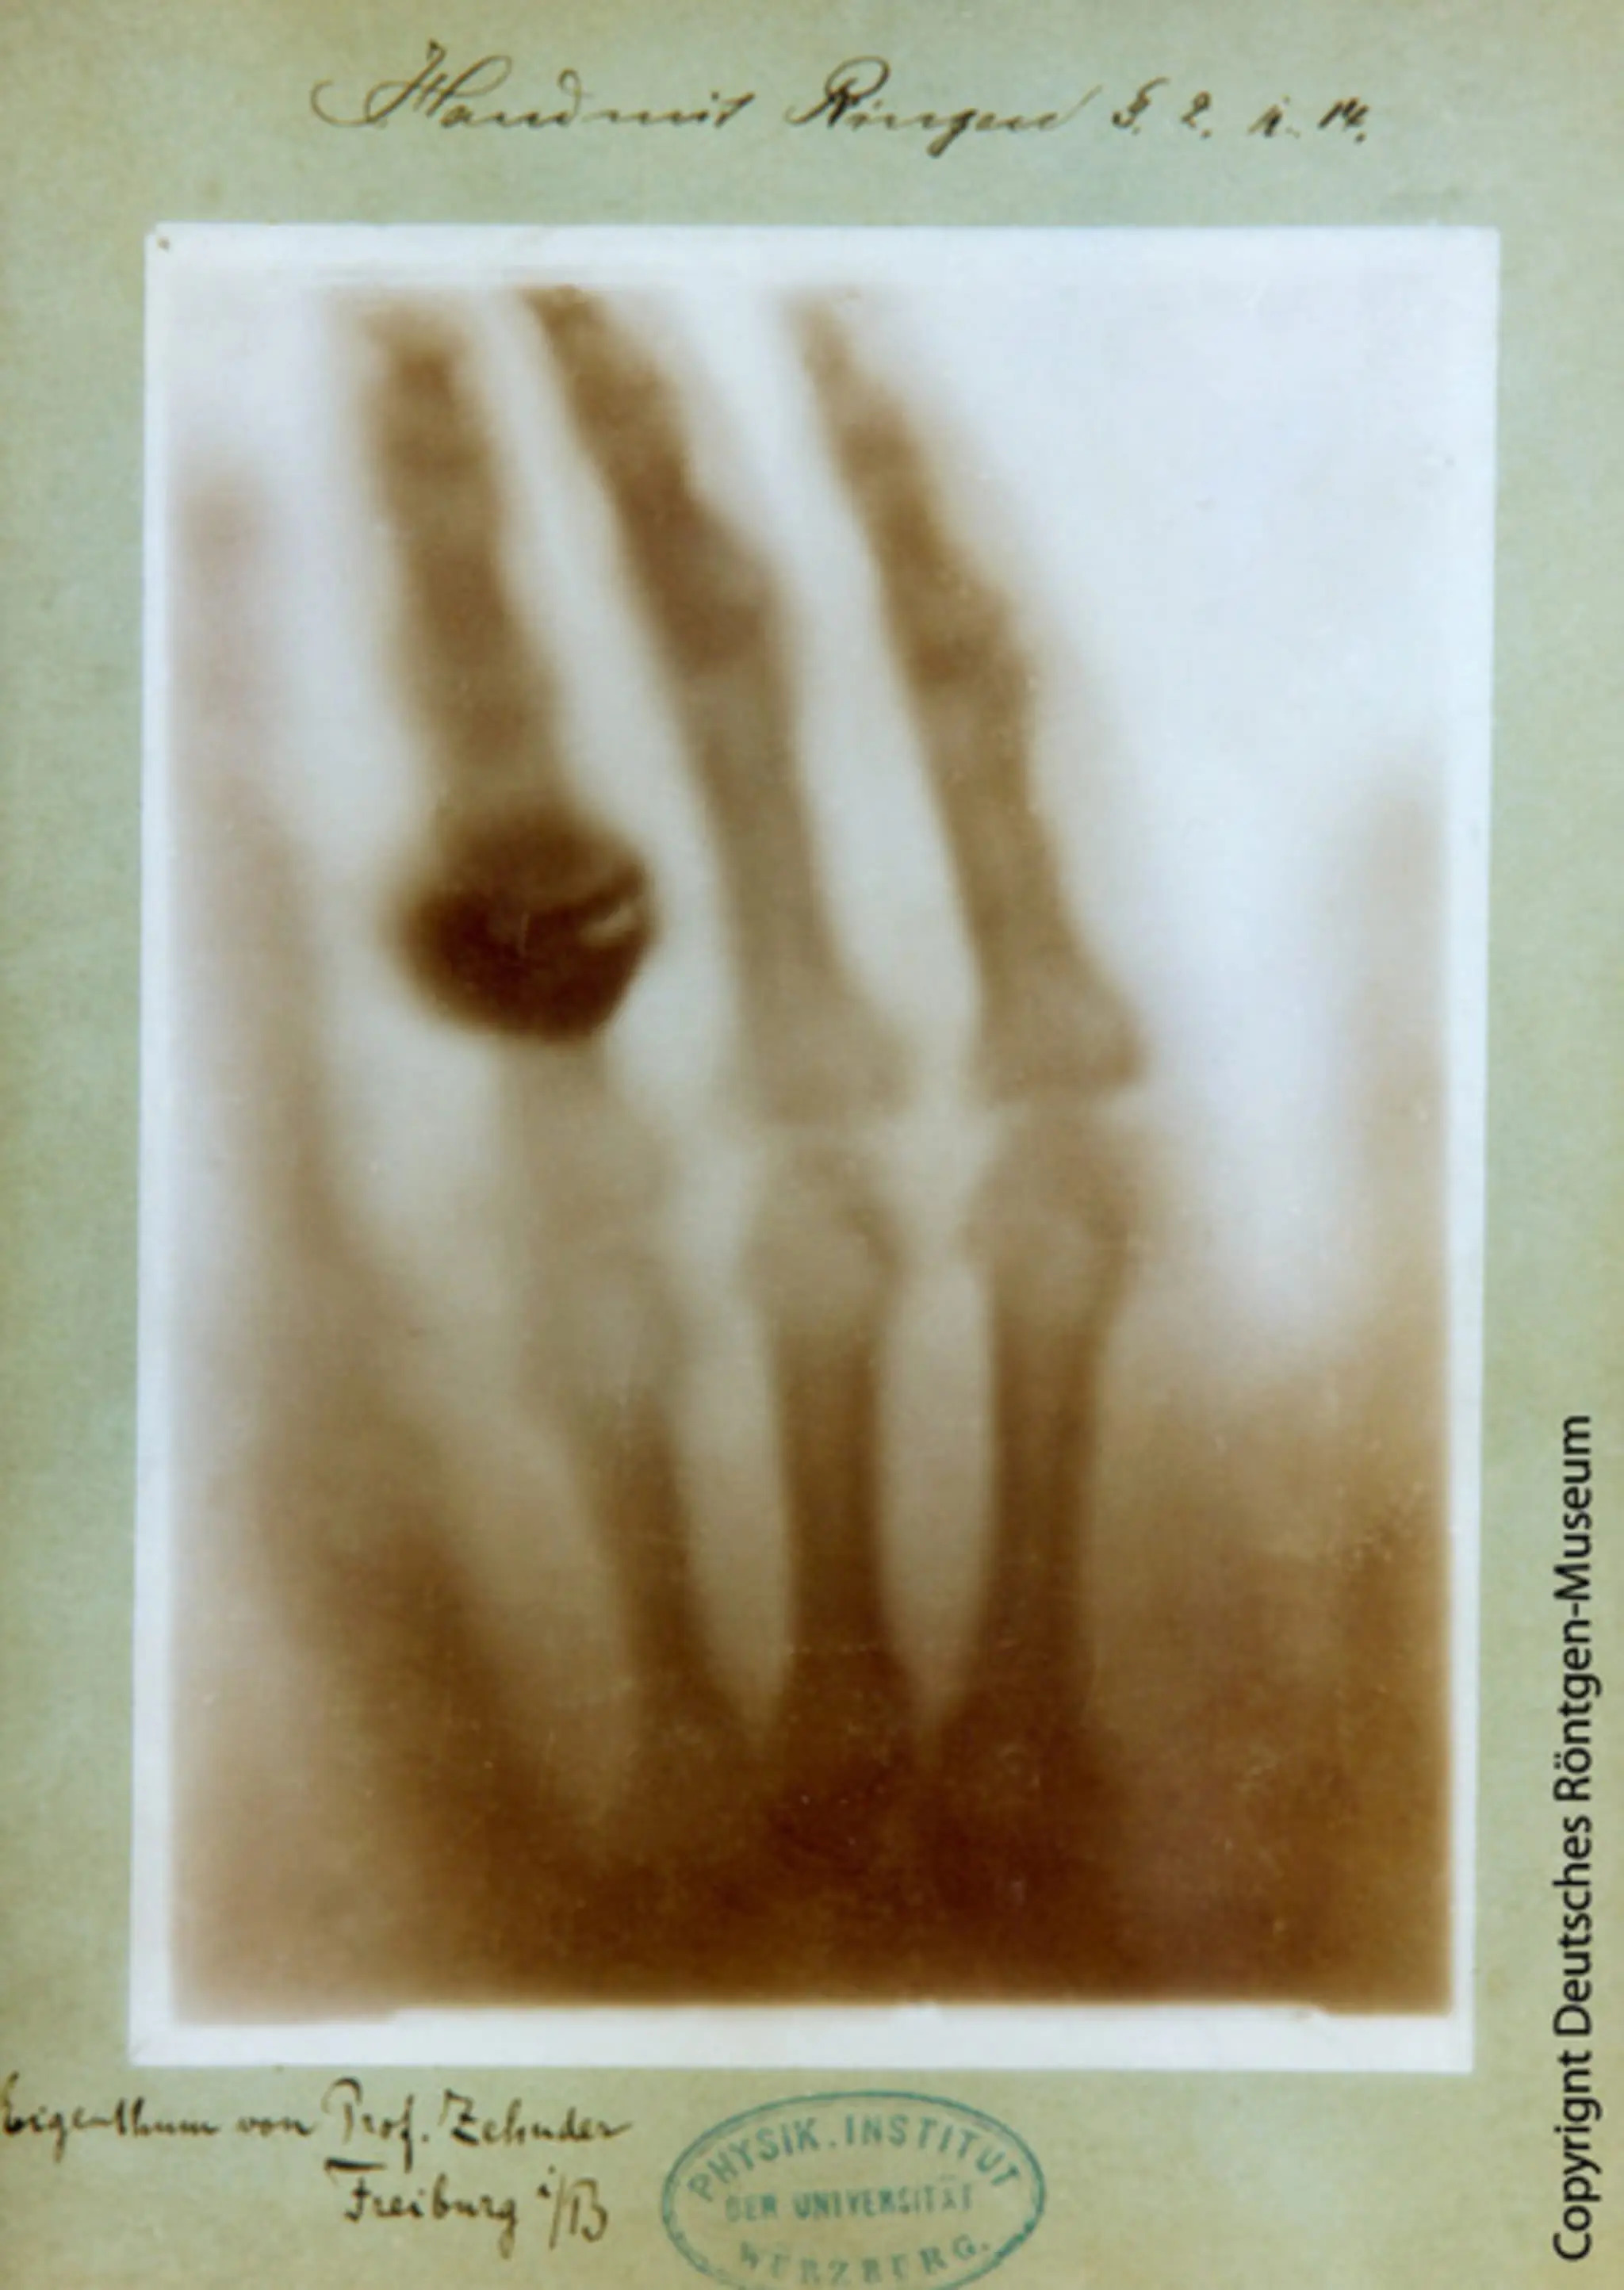

一、世界上的第一张X射线照片,所摄为伦琴妻子的手,1895-12-22

图1 X射线照片:伦琴妻子的手

图3 X射线照片:伦琴妻子的手

图3 Bertha-Roentgens-Hand-1895-copy-Deutsches-Roentgenmuseum

Die wohl berühmteste Röntgen-Aufnahme: Berta Röntgens Hand am 22. Dezember 1895. (Foto: Deutsches Röntgen Museum)

也许最著名的X光照片:Berta Röntgen的手,1895-12-22。 (图片来源:德国X射线博物馆)

Fig. 2 Left: X-ray of Anna Bertrand Röntgen’s hand (1895-12-22). Right: X-ray of Albert von Kölliker’s hand (1896-01-23).

Left: X-ray of Anna Bertrand Röntgen's hand (1895-12-22). Right: X-ray of Albert von Kölliker's hand (1896-01-23).

左图:安娜·柏莎·伦琴的手部X光片(1895-12-22)。右图:阿尔伯特·冯·Kölliker手部的X光片(1896-01-23)。

注:安娜·柏莎·伦琴,即伦琴(Wilhelm Conrad Röntgen)夫人。